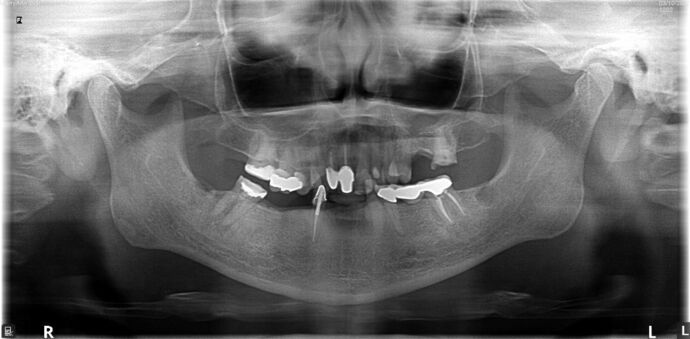

All-on-4/ Full Mouth Dental Implants / Teeth in a Day: Case 20-Gummy smile and failing teeth treatment with Upper and Lower All-on-4 Bridges

This high school teacher was embarrassed about losing her teeth one at a time and had multiple infected teeth causing her pain. She was also unhappy with her gummy smile and found Dr Bidra online. She was informed by 2 other dentists that her gummy smile could not be corrected by dental implants. Dr. Bidra was able to successfully accomplish all her treatment goals by extracting all her teeth and installing Upper and Lower All on 4 implant bridges

Procedures : extractions, gummy smile, new implants, All on 4 , Teeth in a day, no bone grafting and full mouth reconstruction with monolithic zirconia bridges.